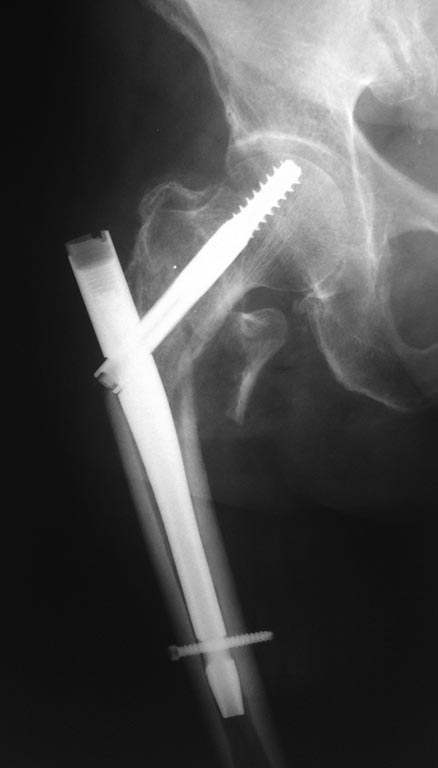

Пациентка В., 75 лет, без выраженной коморбидности, получила травму в

августе 2014 года, диагностирован "Закрытый чрезвертельный перелом

правой бедренной кости со смещением отломков", была прооперирована,

выполнена закрытая репозиция, интрамедуллярный остеосинтез правой

бедренной кости проксимальным бедренным штифтом.

К сожалению, первичных снимков не предоставлено, имеются 2 снимка, через

1 месяц после операции, в сентябре 2014 и второй снимок, в январе 2015,

пациентка на данный момент передвигается с помощью ходунков, отмечает

болезненность при движениях и пальпации, объясняет -

"Как-будто кость упирается в железку". Не хочется говорить о

неправильной технике и cut-out и/или cut-through синдроме, интересно -

что можно сделать и какую тактику лечения выбрать.